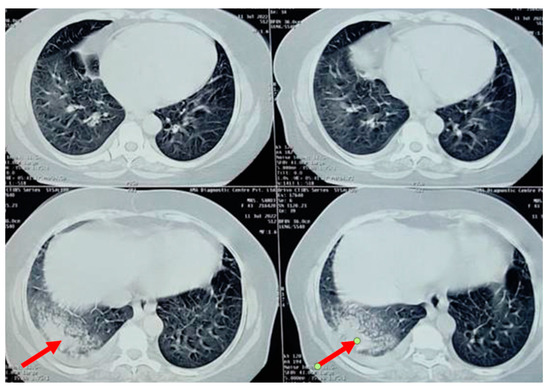

A chest radiograph showed patchy consolidation in the right lower lobe and mild pleural effusion. To obtain a better view of the lesion, a high-resolution computed tomography scan was performed, which showed patchy foci of air space consolidation in the right lower lobe along with pleural effusion (Figure 1).

The patient developed a dry cough after receiving her fourth cycle of chemotherapy and was hence referred to our side for the same. Since none of the routine investigations were successful in identifying a cause for the condition, specific tests like mycoplasma pneumoniae antibodies, rheumatic factor, and antinuclear antibody tests were conducted, and the results were negative. A repeat chest radiograph revealed non-segmental patchy air space consolidation areas in the right lung’s lower zone. The high-resolution computed tomography scan of the thorax also revealed similar findings like areas of “ground glass” opacities at the base of the right lung, with patchy foci of air space consolidation, mostly in the subpleural region (Figure 1). Due to inconclusive evidence from blood and radiological investigations, a decision was made to subject the patient to bronchoscopy.

Figure 1. High-resolution computed tomography scan of the thorax of a 58-year-old female showing right lower lobe consolidation with “ground glass” opacity, indicated by the red arrow (trastuzumab-induced).